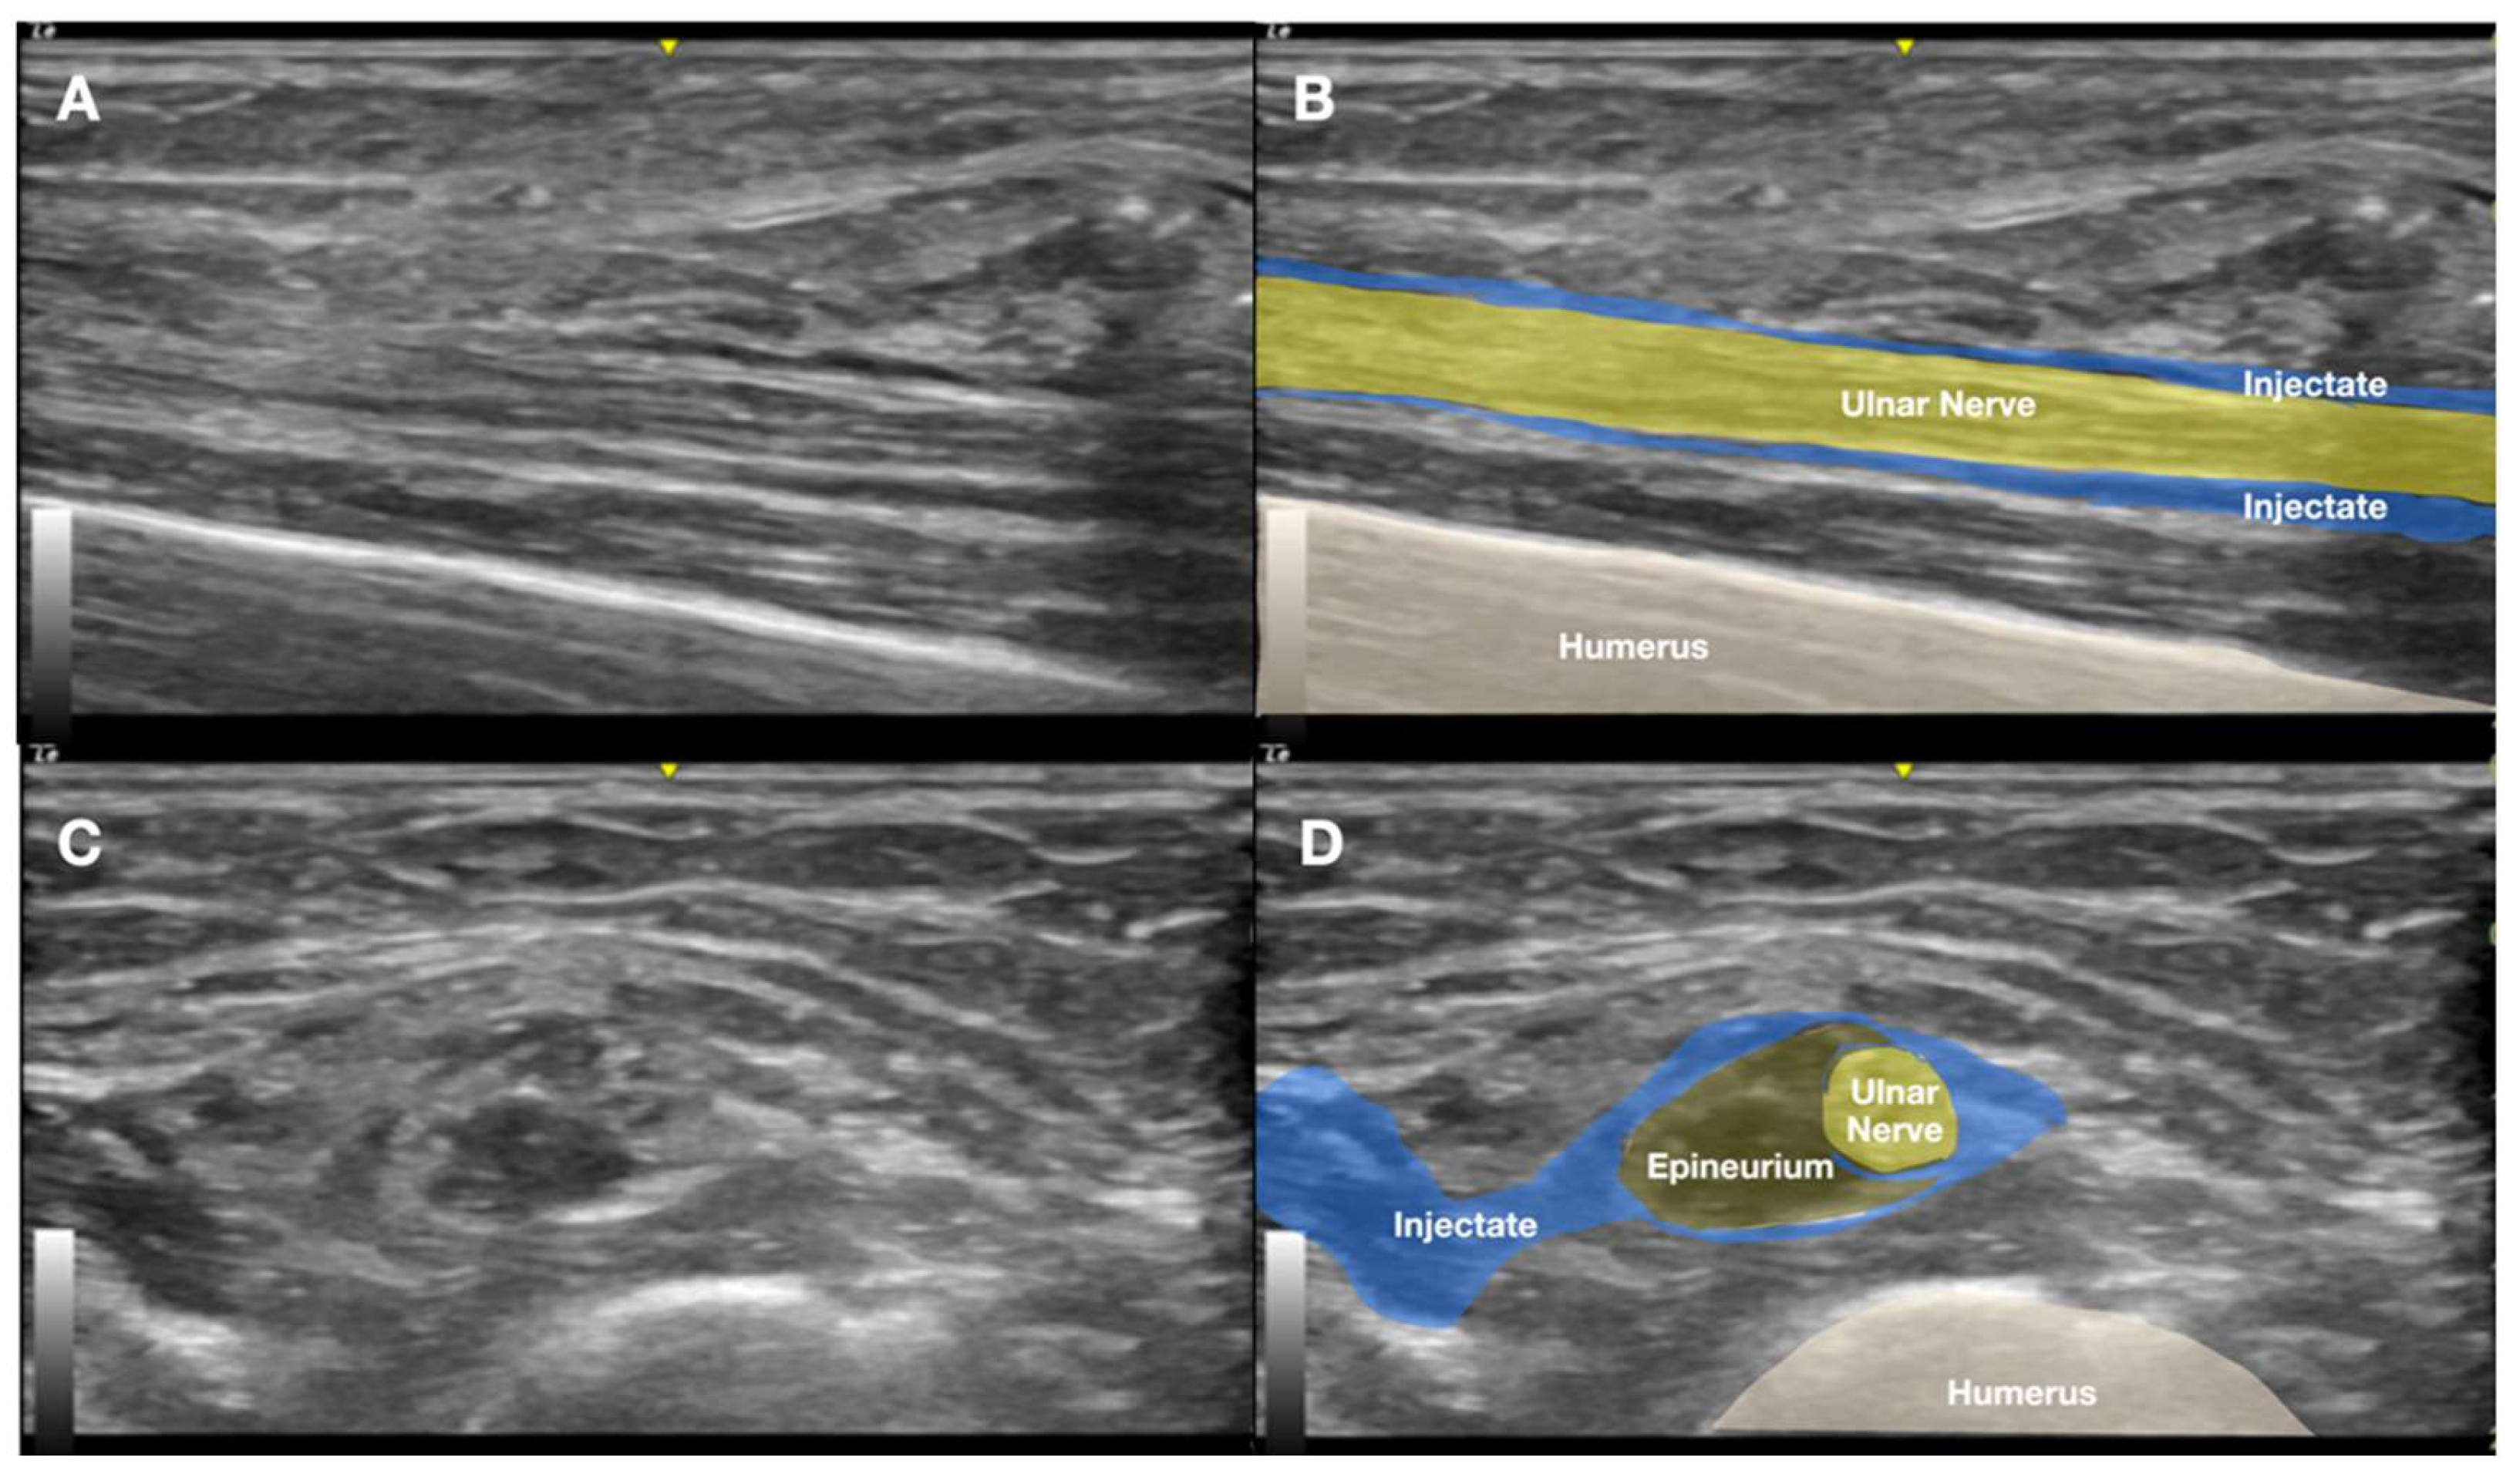

2.1. Prior Imaging Included Radiography (Figure 3), Which Confirmed the Implant’s Location, and Ultrasound (Figure 4), Which Demonstrated Its Proximity to the Ulnar Nerve

2.2. The Procedure